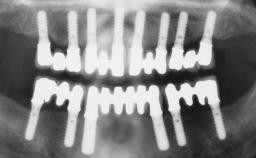

A 56-year-old female patient was referred to the clinic because of retention problems with her mandibular denture. She had been completely edentulous for more than 33 years and wore her sixth set of complete conventional dentures, which had been delivered 5 years previously. An oral surgeon had performed a vestibuloplasty in the interforaminal region of the mandible with a piece of skin tissue 12 years earlier. The panoramic radiograph and lateral cephalometric radiograph exhibited the hypotrophy of the inferior alveolar process. The mandible was a Cawood class VI,and the height of the mandible in the interforaminal zone was 15 mm.

# of Implants 2

Modality 2 interforaminal implants

Bone Volume Horizontally and vertically sufficient